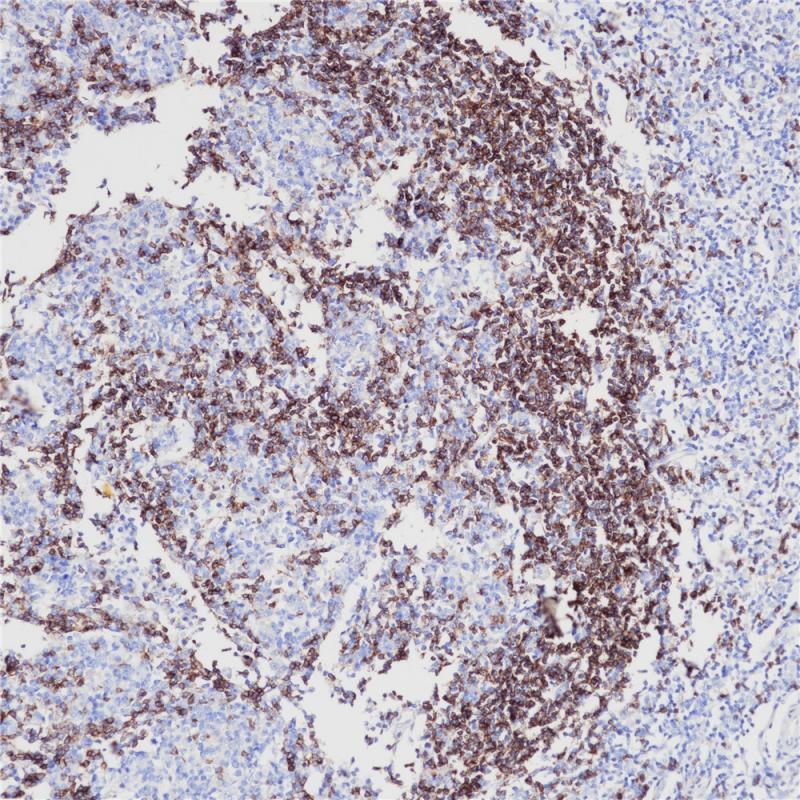

IgD抗体可以与免疫球蛋白IgD的δ链反应,用于淋巴瘤、浆细胞瘤和B细胞来源的霍奇金淋巴瘤的鉴别诊断

阳性对照

扁桃体